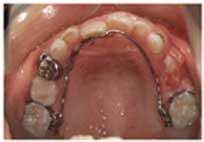

この治療はリンガルアーチという装置で行っています。細い針金で動かした後、歯が後ろに戻らないように、止めています。